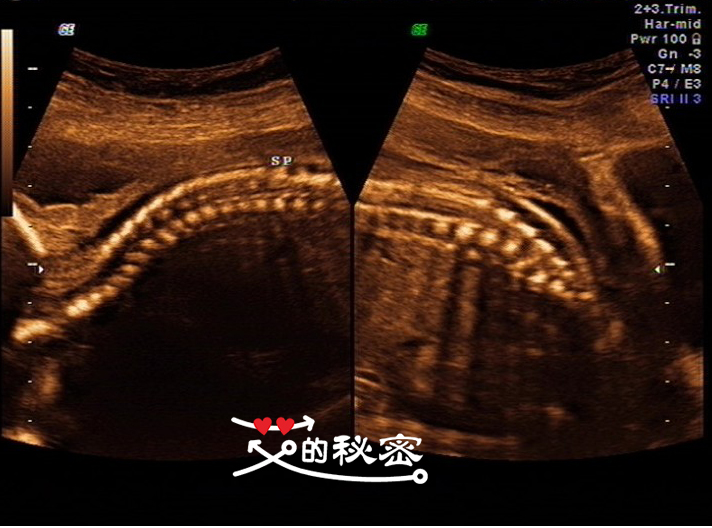

10、胎儿脊柱:颈、胸、腰、骶尾段排列形态未见明显异常,SP表示脊柱的意思。

6、脊柱畸形的筛查是要重点观察脊柱有无隆起,光带有无中断,排列有无紊乱,骶尾部有无肿块等。